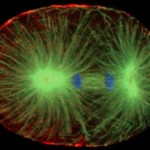

Durante la división celular, las células forman el huso mitótico microtúbulos basado en una estructura altamente especializada y dinámica que ayuda en la transmisión de los cromosomas adecuado y equitativo a las células hijas, dijo Torres. Un enfoque en el tratamiento del cáncer ha sido la meta dinámica de los microtúbulos o vástagosí mismo.

Torres y su equipo trataron de identificar y caracterizar las proteínas necesarias para el ensamblaje del huso, y por lo tanto vital para la división celular. Se realizó una pantalla de alto rendimiento proteómicos para encontrar las proteínas asociadas al cabezal y descubrió 592 proteínas. No estaba claro, sin embargo, si todas las proteínas eran necesarias para el funcionamiento adecuado del husillo.